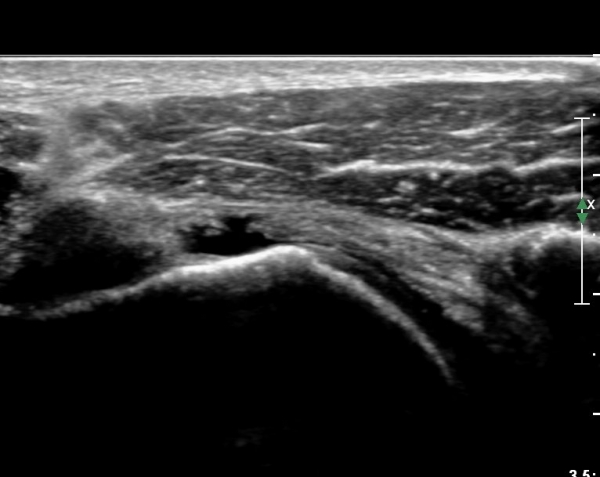

ÃÊÀ½ÆÄ ¼Ò°ß :  È¸Àü±Ù°³°£°Ý °Ë»ó»ó ±Ø»ê°ÇÀº Á¤»ó¼Ò°ßÀ» º¸À̳ª °ß°©ÇϱٰÇÀº Àú¿¡ÄÚ ¿¬°á¼º ¼Ò½ÇÀÌ

º¸¿© °ß°©ÇÏ±Ù°Ç ÆÄ¿­ÀÌ ÃßÁ¤µÈ´Ù(»çÁø 1). ŽÃËÀÚ¸¦ ¾à°£ ¾Æ·¡·Î À̵¿ÇÑ ÈÄ